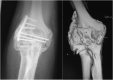

Upper extremity function is highly dependent on elbow motion in order to adequately position the hand in space. Loss of this motion due to stiffness following trauma can cause patients substantial disability, leading to difficulties with performing activities of daily living. Post-traumatic elbow stiffness is challenging to treat, and therefore prevention is of paramount importance. Key measures that can be used to prevent elbow stiffness are early surgical intervention for fracture or joint instability, as well as active mobilisation, which helps to prevent oedema and an increase in viscosity of inflammatory exudates. Other options include splinting and continuous passive mobilisation. Once non-operative methods of addressing post-traumatic stiffness have been exhausted, arthrolysis of the stiff elbow can be performed via open or arthroscopic means depending on the type of pathology involved (intrinsic or extrinsic contracture) and experience of the surgeon with elbow arthroscopy. The particular open approach used depends on several factors, which include the formation and location of any heterotopic ossification present. Improvements in range of motion can be expected with both open and arthroscopic techniques, which can be effective and rewarding for patients. Post-operative rehabilitation, particularly early active mobilisation, should be considered essential in order to optimise patient outcomes following surgery. This review aims to explore elbow stiffness following traumatic aetiology, assessing its pathogenesis and prevention, as well as reviewing surgical treatment options and post-operative rehabilitation.